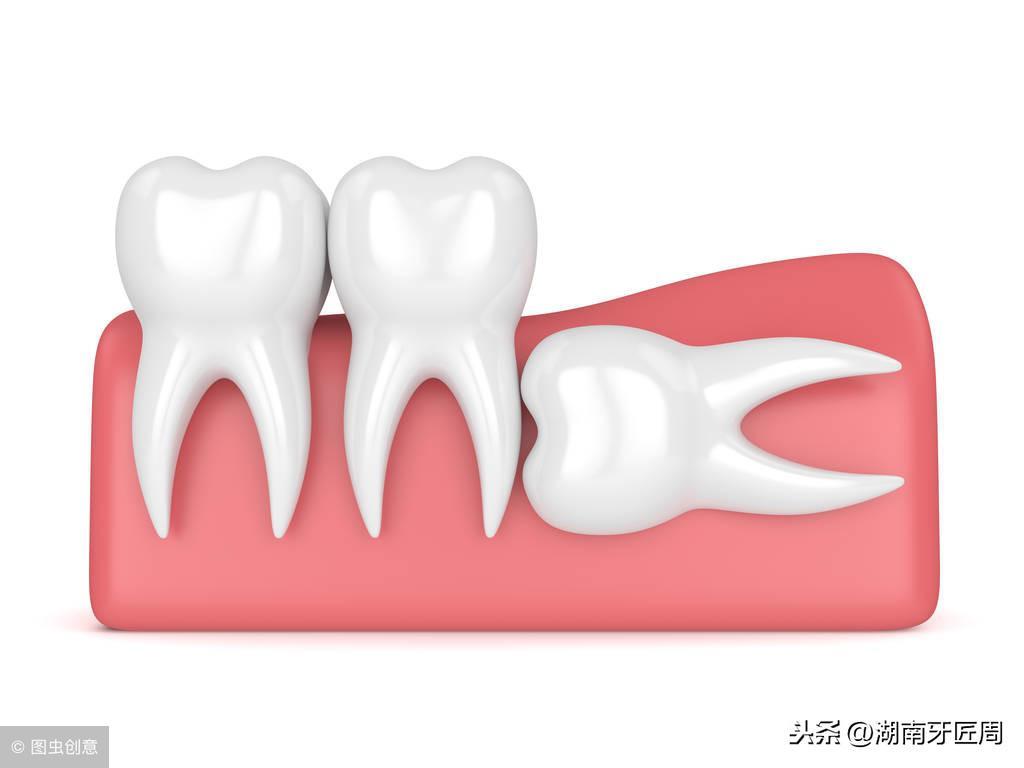

左侧智齿倾斜阻生,顶坏前牙

下颌骨结构得不到充分的咀嚼功能锻炼,逐渐退化,牙量大于下颌骨量,这样当第三磨牙长出时就常常位置不够,以致萌出困难,这就形成了“智齿阻生”,智齿阻生是青壮年人的一种常见病。

下颌智齿能够正常萌出并且有正常的咬颌关系者仅仅占很少数,“智齿”萌出时由于没有足够的空间,很容易长歪,例如出现向颊侧或者舌侧倾斜、向前后倾斜等情况。